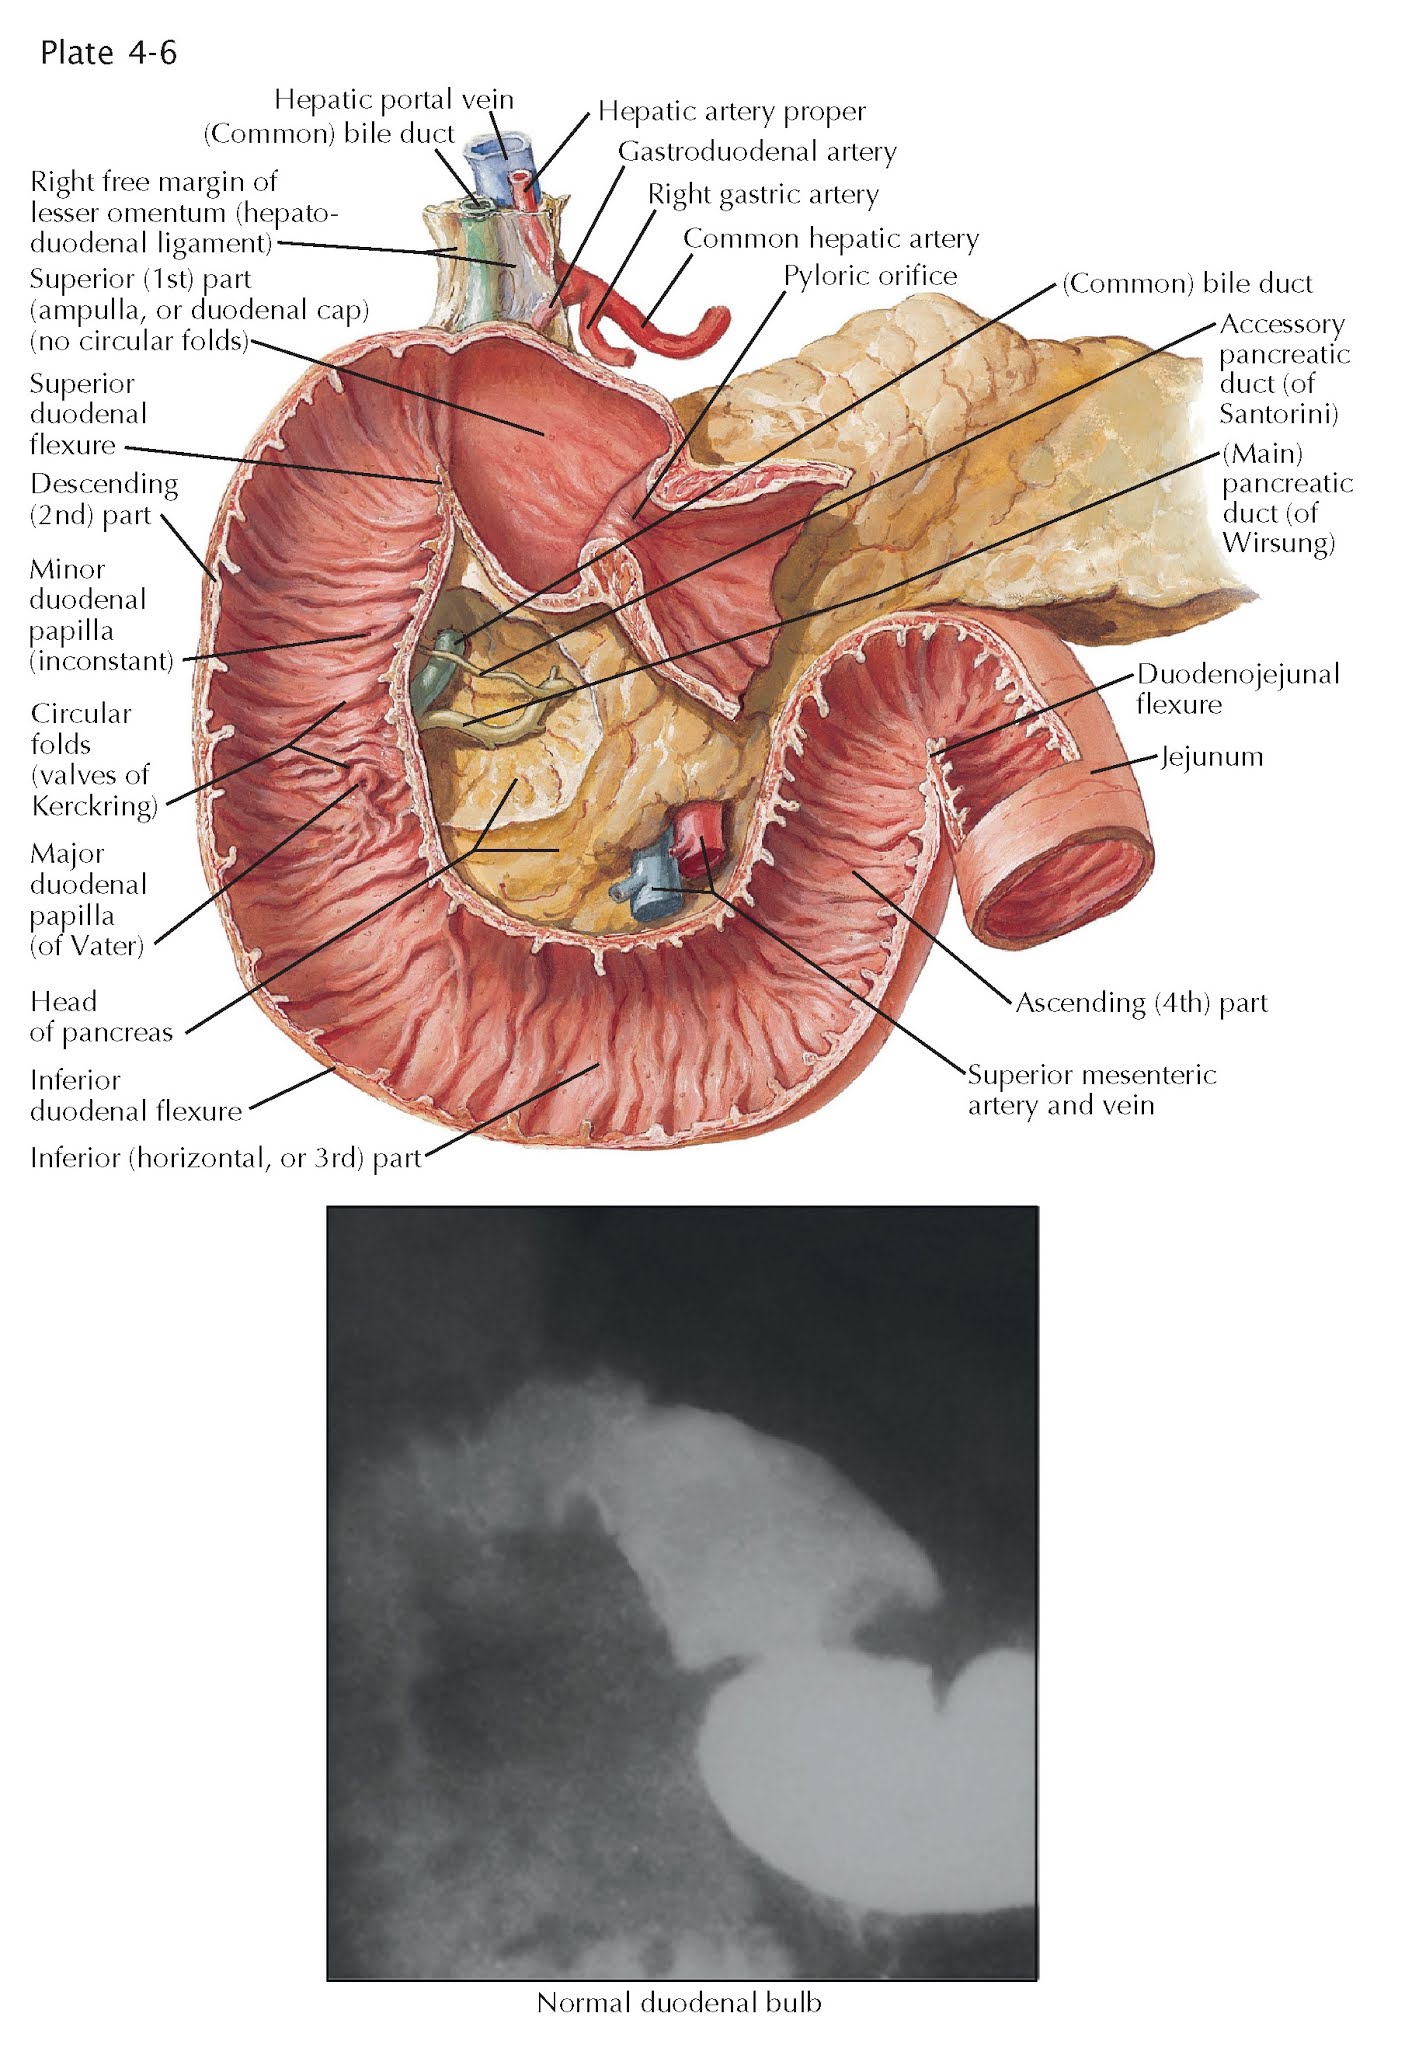

DUODENAL BULB AND MUCOSAL SURFACE OF DUODENUM

The mucosa of the widened first portion of the duodenum, known also as the duodenal ampulla (cap, bulb), is relatively flat and smooth except for a few small longitudinal folds. Except for the smooth duodenal ampulla, the mucosal surface of the duodenum, which in living subjects is reddish in color, is lined with villi, giving the small intestines their velvety appearance. The mucosa of the distal duodenum is nearly identical to the small intestine with circular folds (of Kerckring) projecting into the lumen. These folds, which considerably increase the surface area of the intestine, begin in the region of the superior duodenal flexure, increasing in number and elevation in the more distal parts of the duodenum. They do not always form complete circles along the entire intestinal wall, because some are semicircular or crescent shaped, whereas others branch out to connect with adjacent folds. Very often they deviate from their circular pattern and pursue a more spiral course. The circular folds are large macroscopic structures and include mucosa and submucosa in their core. The more superficial layers of the duodenum, the muscularis externa and adventitia, are not included in the circular folds.

Approximately halfway down the posteromedial aspect of

the descending part of the duodenum, a distance of approximately 8.5 to 10 cm

from the pylorus, is located the major duodenal papilla, also known as

the papilla (of Vater). This is where the common bile duct and

the major pancreatic duct (of Wirsung) open into the duodenum. The

common bile duct approaches the duodenum within the enfolding hepatoduodenal

ligament of the lesser omentum and continues inferiorly in the groove between

the descending portion of the duodenum and the pancreas. The terminal part of

the common bile duct produces a slight but perceptible longitudinal impression

in the posteromedial duodenal wall known as the longitudinal fold of the

duodenum. This fold usually ends at the papilla but may occasionally

continue for a short distance beyond the papilla in the form of the so-called

frenulum. Small hoodlike folds at the top of the papilla protect the mouth of

the combined bile duct and pancreatic duct. A small, wartlike, and generally

less distinct second papilla, the minor duodenal papilla, is situated

about 2.5 cm above and slightly medial to the major papilla. It serves as an opening for the minor

pancreatic duct (of Santorini).

The duodenal ampulla, varying in form, size, position,

and orientation, appears in an anteroposterior radiograph as a triangle, with

its base at the pylorus and its tip pointing toward the superior flexure of the

duodenum. The duodenum’s longitudinal folds, as well as the circular folds in

the lower parts of the duodenum, can be visualized radiographically if a barium

meal of appropriate quantity and consistency is given. In such a relief picture

of the mucosa, the region of the major duodenal papilla occasionally appears as

a small, roundish filling defect. When the papilla is enlarged in the form of a

small diverticulum, the contrast medium may sometimes enter the terminal

portions of the bile and pancreatic ducts, with the result that on the x-ray,

this area l oks like the shape of a molar tooth with two roots.